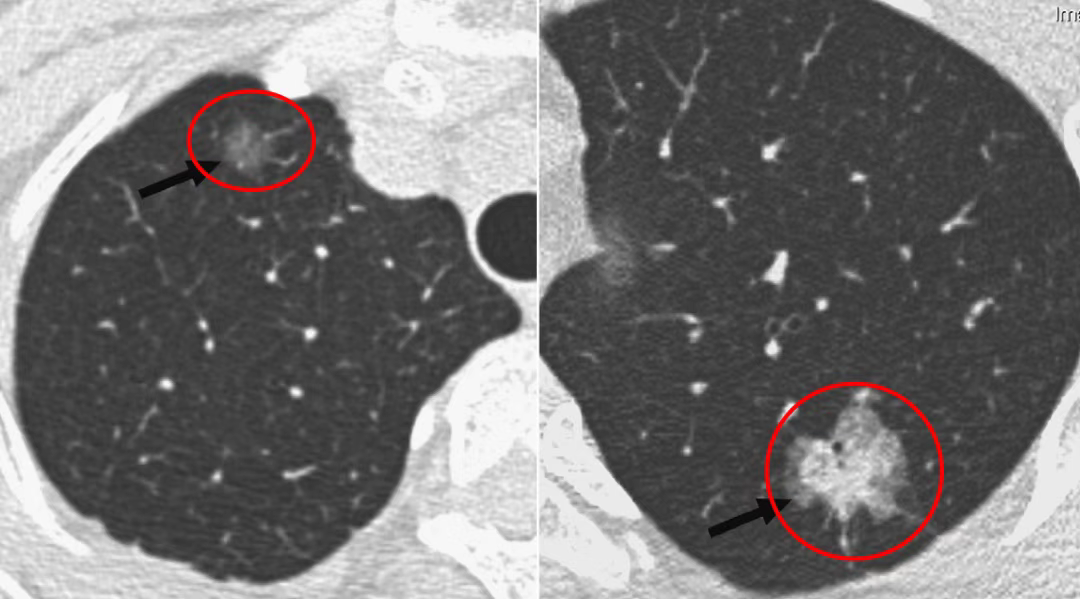

图左左肺下叶浸润性腺癌,病灶呈现出不规则GGN表现,边界清晰,有毛刺和分叶征

图右左肺上叶前段浸润性腺癌,轴位示不规则GGN表现,边界清晰,有分叶和胸膜凹陷征